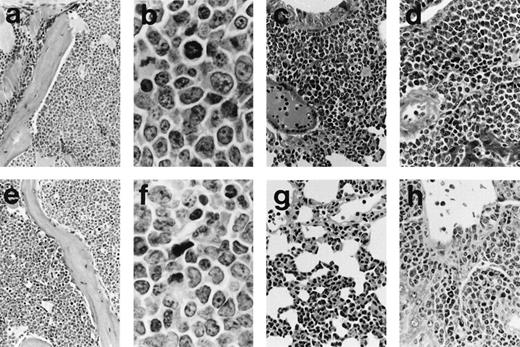

Histopathological and flow cytometric evaluation of tissues taken at postmortem and serial transplantation showed that the MSCV-FL mice had developed B-cell and/or myeloid leukemias. Splenomegaly (∼5-fold enlargement; average spleen weight of 0.48 ± 0.05 gv 0.09 ± 0.02 g in controls), invasion of the lungs and liver (Fig 3), and colonization of the bone marrow by the tumors were frequently observed, along with some lymph node infiltration (see Fig 8) but no or minimal involvement of the thymus. The phenotype of representative leukemias was evaluated by immunofluorescence flow cytometric analysis of spleen cell suspensions using monoclonal antibodies recognizing hematopoietic cell surface antigens. The analysis demonstrated heterogeneous expression of markers characteristic of the B-lymphoid and myeloid lineages, including the B-lineage marker B220/CD45R, the myeloid differentiation antigen Mac-1/CD11b, the granulocyte marker Gr-1/Ly-6G, and the monocyte/macrophage differentiation antigen Ly-6C, as well as low-affinity Fc receptors for IgG FcγRII/III and the heat-stable antigen HSA/CD24 found on cells belonging to both lineages (data not shown). Although the heterogeneity was likely due in part to reactive cells, double staining with antibodies against B220 and Mac-1 showed a minor subpopulation in some of the tumors that was positive for both markers (Fig 4), suggesting that, in these cases, a precursor common to the B-cell and myeloid lineages was the target cell for transformation. To further investigate this possibility, we transferred serially transplanted tumors to culture (see Materials and Methods). Three of the four leukemic populations studied in detail (196-, 199-, and 203-series cells) preferentially expressed B220 or Mac-1 after several weeks in vitro, whereas the majority of cultured 204-series cells coexpressed B220 and Mac-1 (Table 2).

Histology of representative leukemias arising in MSCV-FL mice. Hematoxylin and eosin-stained sections are shown for mouse 196 with B-lymphoid leukemia (a through d) and for mouse 199 with biphenotypic leukemia (e through h). (a) The bone marrow architecture of mouse 196 is effaced by a blast cell infiltrate that extends into the adjacent muscle (original magnification × 185). (b) At higher magnification, blast cells in the bone marrow of mouse 196 can be seen to be predominantly medium-sized with round to oval nuclei, moderately basophilic cytoplasm, and occasionally with prominent nucleoli; mitotic figures are abundant (original magnification × 1,115). (c) Lung of mouse 196 showing diffuse interstitial and nodular peribronchial parenchymal infiltrates (original magnification × 270). (d) Liver of mouse 196 showing perivascular accumulations of blast cells as well as some blast cells around bile ducts (original magnification × 370). (e) Bone marrow of mouse 199 showing blast cells of variable size occupying the hematopoietic space; scattered erythroblasts and megakaryocytes are present (original magnification × 185). (f) At higher magnification, blast cells in the bone marow of mouse 199 of variable shape with irregular nuclei and one to three distinct nucleoli can be seen to be intermixed with granulocytic cells of various maturational stages (original magnification × 1,115). (g) Lung of mouse 199 showing diffuse interstitial infiltrates of blast cells and granulocytes (original magnification × 270). (h) Liver of mouse 199 showing polymorphous tumor infiltrates, sometimes with pronounced granulocytic differentiation, mainly in periportal areas (original magnification × 370).